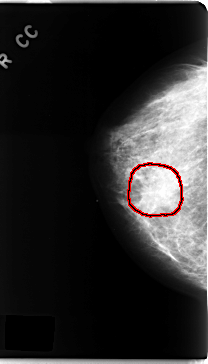

C_0162_1.RIGHT_CC

FILE: C_0162_1.RIGHT_CC.OVERLAY

TOTAL_ABNORMALITIES 1

ABNORMALITY 1

LESION_TYPE CALCIFICATION TYPE FINE_LINEAR_BRANCHING DISTRIBUTION CLUSTERED

LESION_TYPE MASS SHAPE IRREGULAR MARGINS ILL_DEFINED

ASSESSMENT 5

SUBTLETY 4

PATHOLOGY MALIGNANT

TOTAL_OUTLINES 1

BOUNDARY